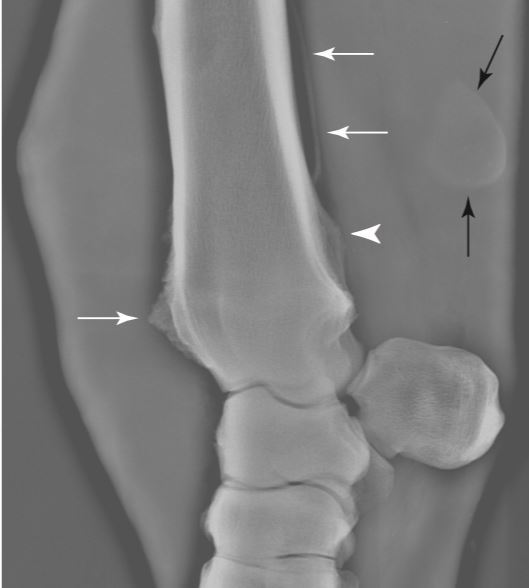

The pictures represents what pathology? The long arrow in A represents what?

This is distal caudal radial physeal exostosis or osteochondroma.

This causes impingment of the DDF causing secondary synovitis.

A is the normal bony prominence of the radius…you need the other osseos shit to make it pathologic.